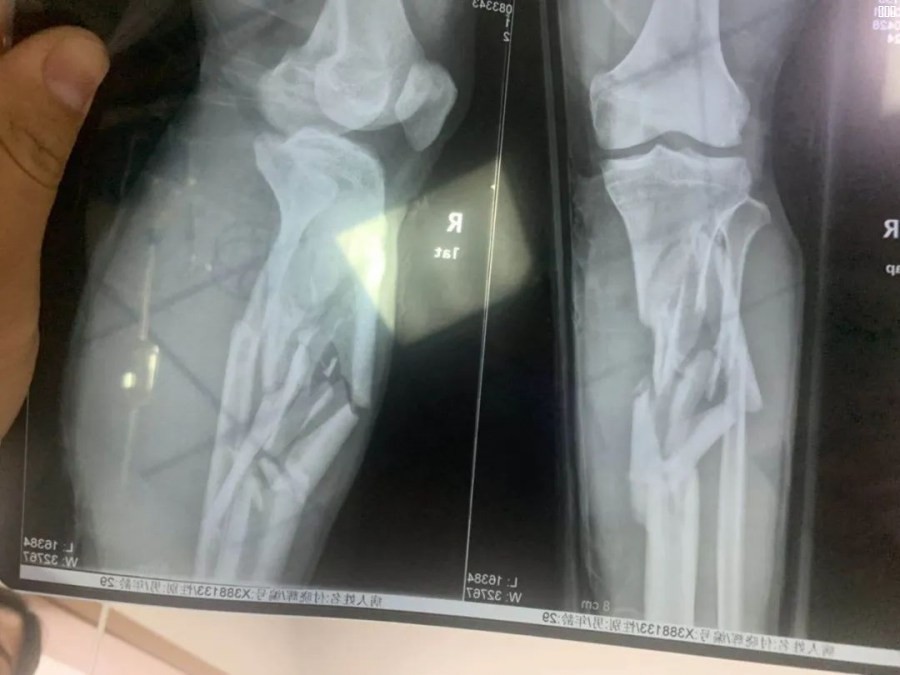

人员受伤情况现在不详,我们在这里也希望不要有严重的问题,静等车主的消息。网络传图可能有误: